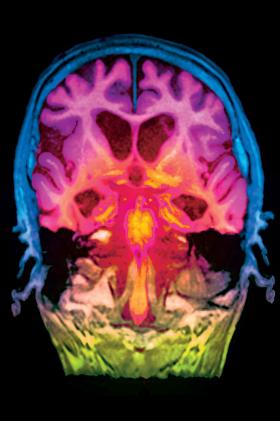

Sztucznie kolorowany obraz przekroju mózgu z objawami choroby Alzheimera uzyskany w rezonansie magnetycznymSovereign/BEW Sztucznie kolorowany obraz przekroju mózgu z objawami choroby Alzheimera uzyskany w rezonansie magnetycznym